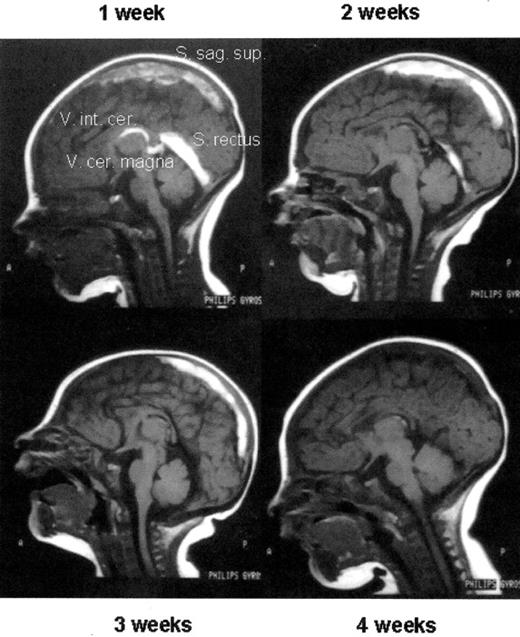

Infusion of deficient inhibitors of hemostasis

In cases of thrombosis with hereditary or acquired deficiencies of coagulation inhibitors, replacement therapy may be an option. Concentrates of AT and PC are commercially available and are life saving in conditions of purpura fulminans due to inhibitor deficiency. PC concentrate also proved to be effective in heterozygous or acquired PC deficiency (Figure 2 ). Fresh frozen plasma is the only but effective option of treating patients with purpura fulminans or hereditary TTP due to PS or ADAMTS13 deficiency, respectively.

Thrombolytic therapy of an extensive sinus venous thrombosis in a newborn with heterozygous protein C deficiency by protein C concentrate after 1 week of ineffective UFH therapy (1 week) and, after initiating protein C replacement, at week 2, 3, and 4 of therapy, respectively. Note the almost complete re-canalization.